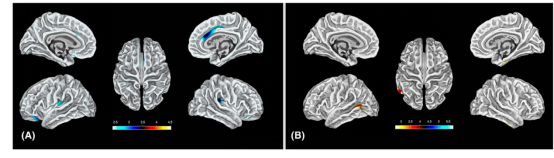

基于表面的形态学测量(SBM)三维伪彩色映射。(A)婴儿痉挛症(IS)< 健康对照(HC)。显示IS组皮层脑沟变浅区域:双侧岛叶、右侧颞极、右侧中央前回、左侧后扣带回及右侧颞下回(p<.001,k>30个体素)。(B)IS > HC。显示IS组皮层脑沟加深区域:左侧前扣带回及左侧额内侧回(p<0.001,k>30)。

SBM三维伪彩色映射。(A)婴儿痉挛症(IS)< 健康对照(HC)。显示IS组皮层皱褶减少区域:双侧岛叶、右侧前扣带回及左侧额下回(p<0.001,k>30)。(B)IS > HC。显示IS组皮层皱褶增多区域:左侧颞中回(p<0.001,k>30)。